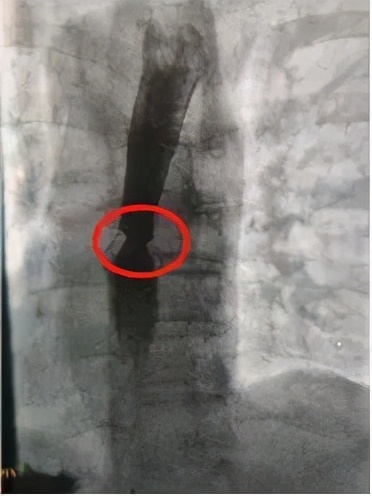

红圈处食道十分狭窄

经过食道造影检查和科室会诊,介入科邵泽锋主任根据朱爷爷的病情、年龄,准备为朱爷爷在食管狭窄处放置一枚食道支架。

放入支架后,狭窄情况有好转